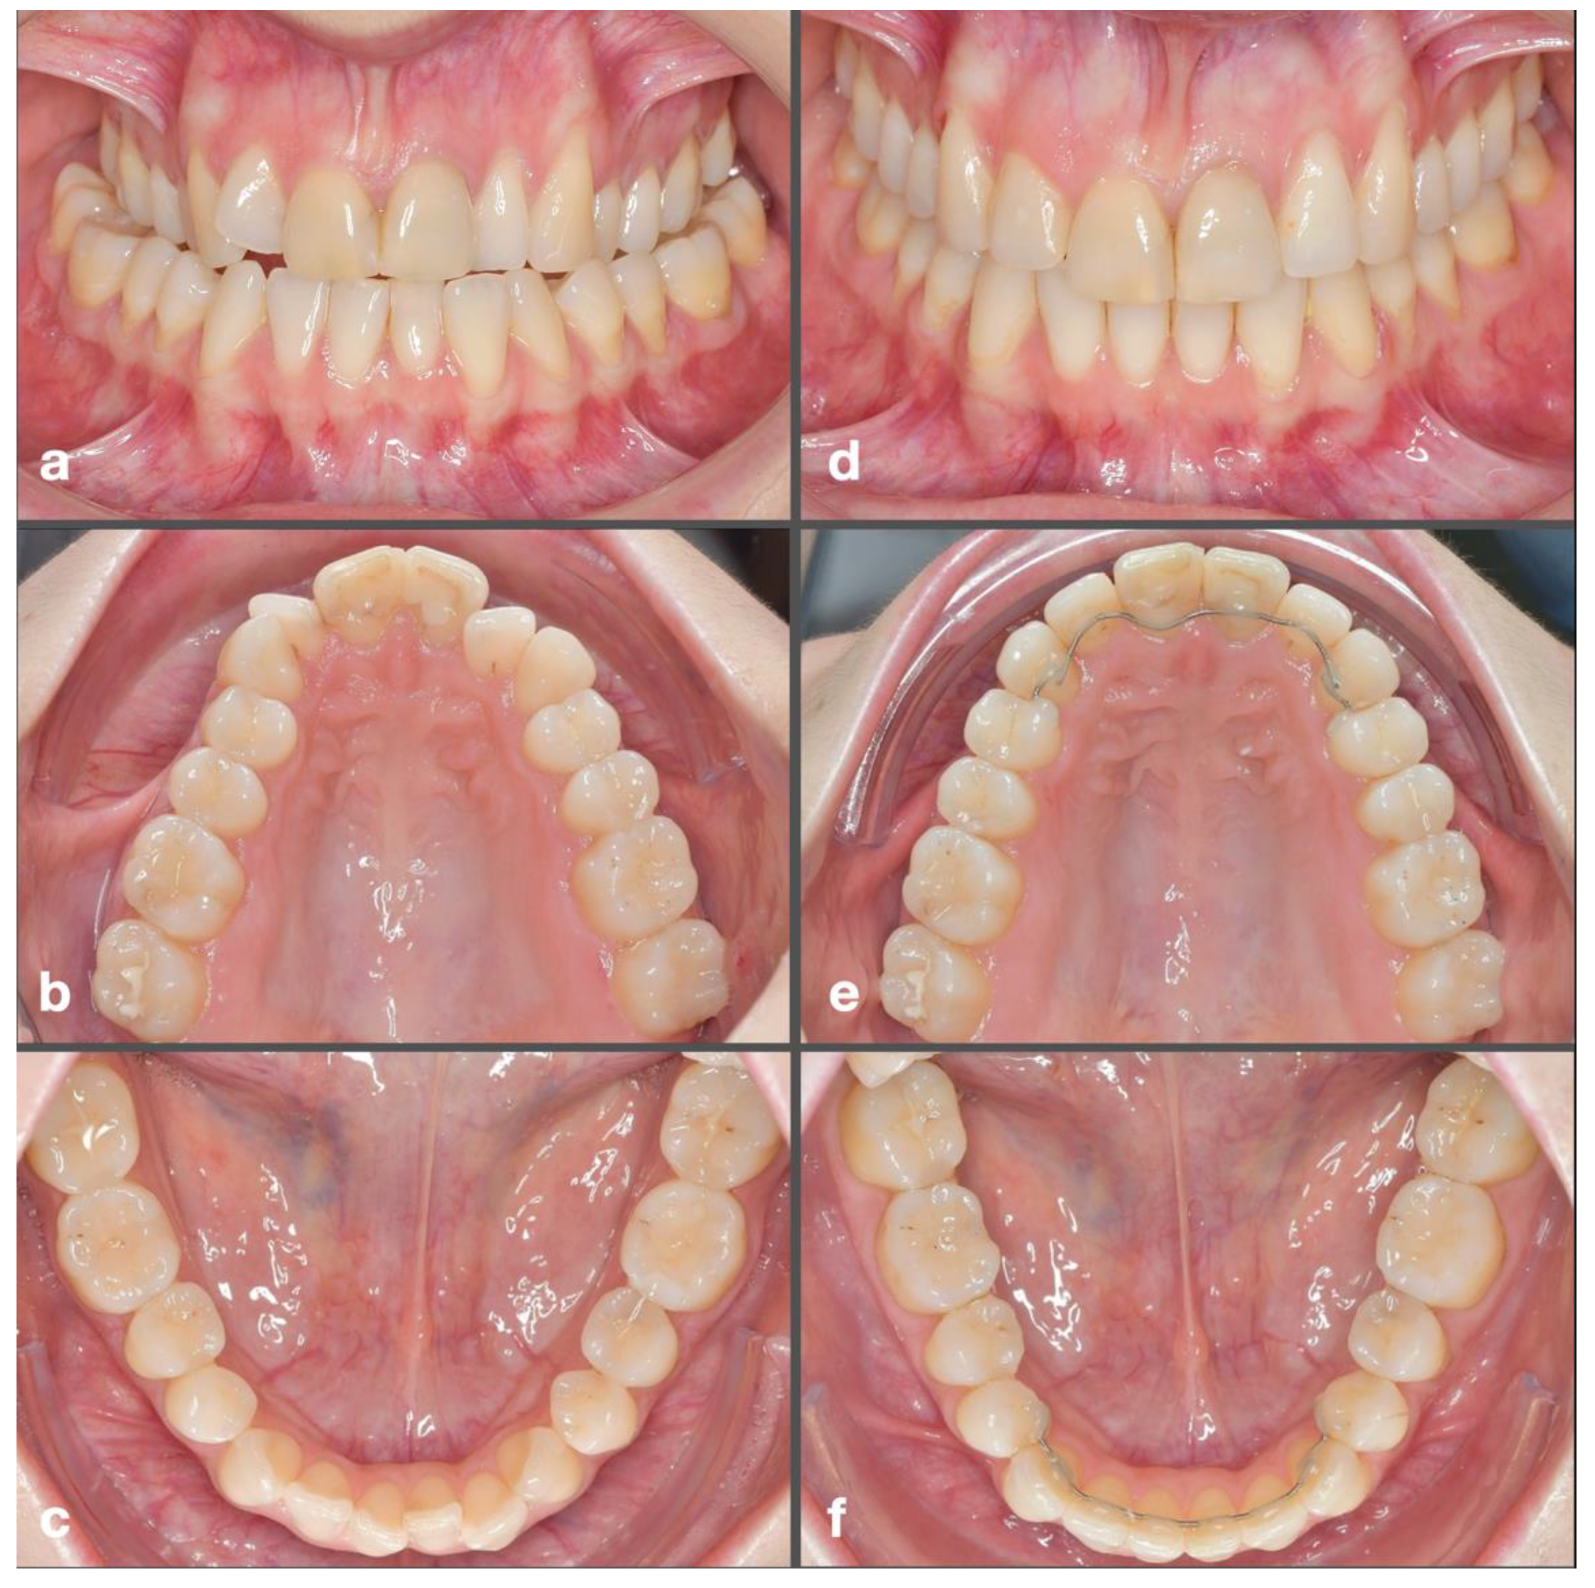

2.1. Measurement Process